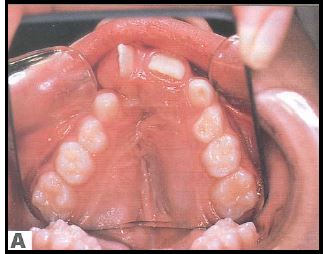

Suulaepoolt lõikunud koonilise kujuga lisahammas

Puudub ülemine tsentraalne intsisiiv

Protseduure nõudvad arenguvead– Suurem osa hammaste arenguvigu ei nõua korrektsiooni.

– Liigne hammas, eriti ülalõua keskjoonel, võib takistada teiste hammaste lõikumist. Niisiis tuleks see eemaldada.